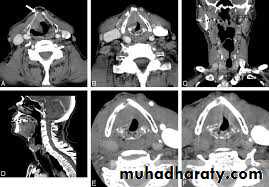

1.Head and facial skeleton: fractures, osteolytic lesions, and hyperostosis.

2. Intracranial lesions: hematoma, infarction, abscess, tumors.

3. Intraoral mass, paranasal sinuses, larynx, nasopharynx salivary glands.

4. Cervical lymphadenopathy and neck masses.

5. Effective means of guiding the placement of FNA for biopsy.

6. Angiography (using contrast agent).